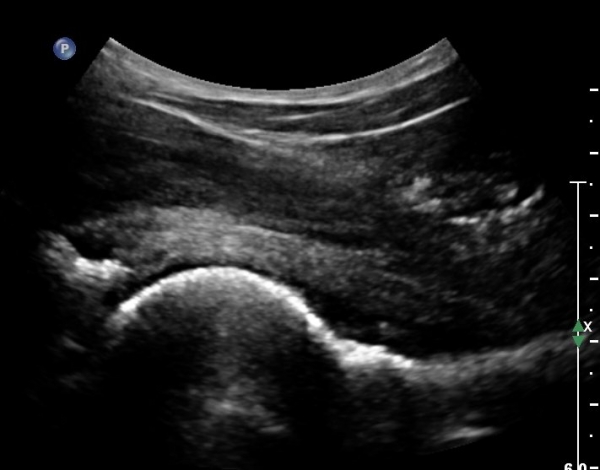

°í°üÀý À§, ¿ÜÃø¿¡¼­ ´ëÅðÁ÷±Ù Á¾´Ü¸é°Ë»ç»ó  ´ëÅðÁ÷±Ù °ðÀº ¼¶À¯(direct) ±â½ÃºÎ¿¡ ¹Ì¼¼ÇÑ

¼®È¸¼º º´º¯À» º¸À̳ª ÈûÁÙÀÇ Àú¿¡ÄÚ ºÎÁ¾Àº °üÂûµÇÁö ¾ÊÀ½.(»çÁø 3, 4)